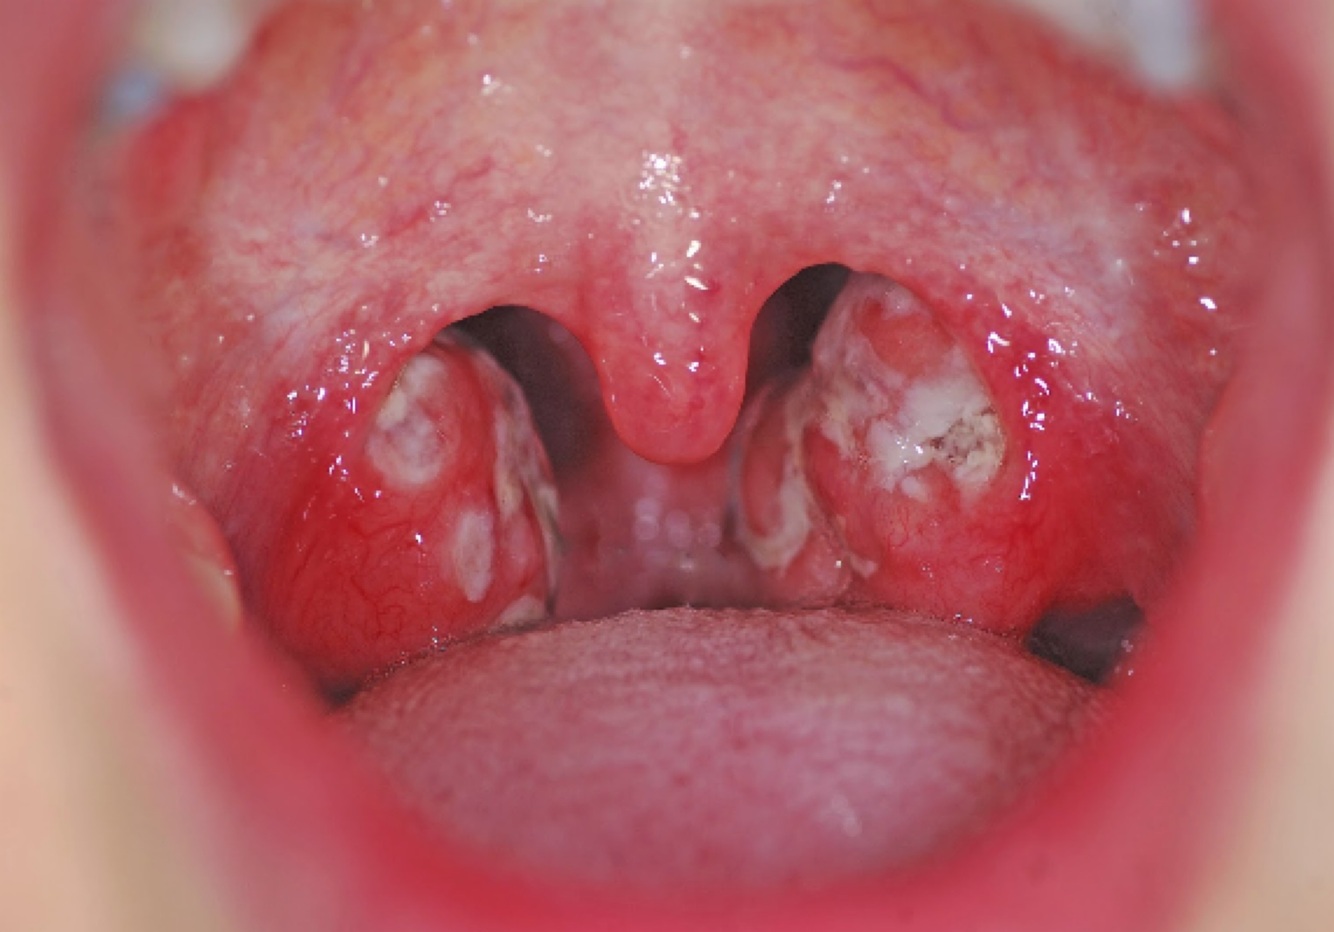

DX

Amigdalitis bacteriana

amigdalitis bacteriana o suprativa